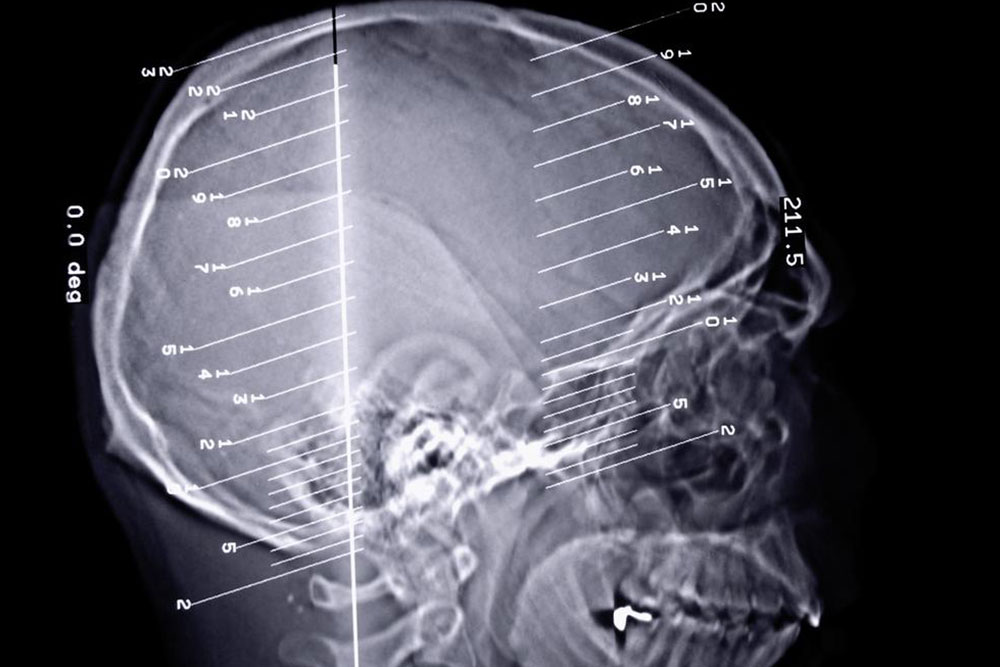

Epilepsy is a dreaded disorder, especially since it is connected to the dysfunctioning of the brain. The brain plays a pivotal role in the functioning of the human body and any kind of issue can lead to severe complications. The disorder is related to the dysfunctioning of the central nervous system in the brain. When the nerve cells in the brain send out wrong signals to the body, the result may be moderate to severe seizure.